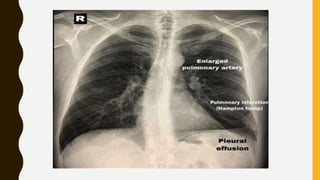

IMAGING

• Chest x-ray is usually normal

Findings, such as

• Focal oligaemia (westermark sign),

• A peripheral wedge-shaped opacity, usually in the

lower half of the lung field (hampton’s hump), or

• An enlarged right descending pulmonary artery

(Pallas’s sign) are rare